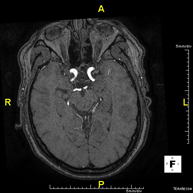

- RM Cerebral (cranial)

Prova diagnòstica no invasiva que consisteix en l'obtenció d'imatges d'alta definició anatòmica del cerbell mitjançant l'ús d'un camp electromagnètic i ones de ràdio (com un emissor i un receptor). No utilitza radiació ionitzant. Indicacions: problemes vasculars, pèrdua de memòria, epilèpsia, cefalea, malformacions, sospita de tumor, meningitis. - RM de Cais